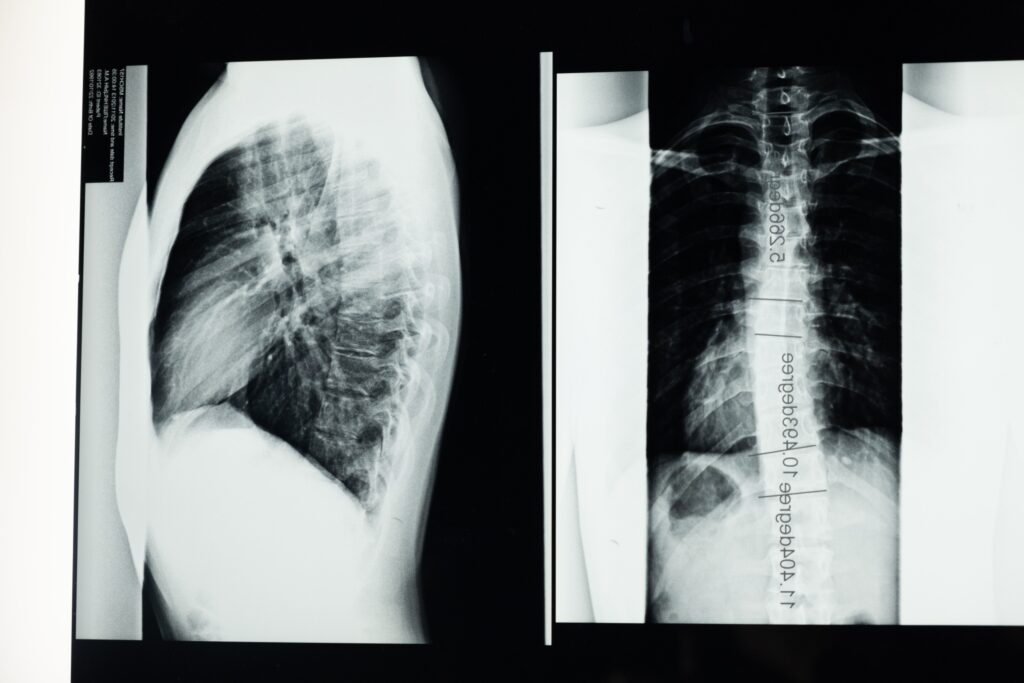

Scoliosis is a diagnosis that involves a curvature of the spine, the bones that run along the middle of your back. If a child is affected with scoliosis, as they grow, their spine will begin to curve in either the cervical, thoracic, or lumbar spinal regions, aka the neck, upper back and lower back regions. Changes in the spine’s natural anatomy create imbalances in the body that may cause your child’s shoulders, shoulder blades, hips, or ribs to look unlevel or uneven. It may also cause their spine to appear curved when bending forward, may affect their overall mobility, and may create back pain later in life if left untreated. If a child’s scoliosis is very severe, it can also affect the shape and growth of their internal organs, like the lungs or the heart.

There are four different types of scoliosis: idiopathic, neuromuscular, congenital and degenerative. Degenerative scoliosis is often diagnosed above the age of 65 due to normal wear and tear on the spine and surrounding joints. Congenital scoliosis occurs as a result of spinal or rib deformities present at birth. Neuromuscular scoliosis can occur when a child has a neuromuscular condition, like cerebral palsy or muscular dystrophy. With Neuromuscular scoliosis, as the child grows, their muscles pull on their bones as they move and continue to participate in developmentally appropriate activities. When a child has a neuromuscular condition, they might not be moving with similar movement patterns or frequency to a child that is developing typically. This means that their muscles are not pulling the same way on their bones as a typically developing child’s muscles are, and this can cause their bones to grow abnormally, creating a potential for scoliosis.